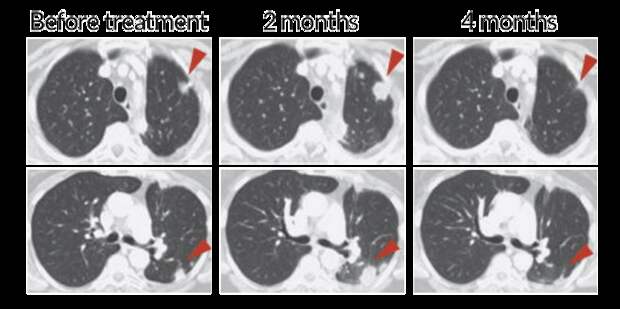

A patient with non-small cell lung cancer received a treatment targeting the T cell protein PD-1, unleashing the cells to fight the cancer. At two months, the T cells have infiltrated the tumor (red arrows), making it appear bigger. But at four months, the immune cells’ continued attack has shrunk the tumor.